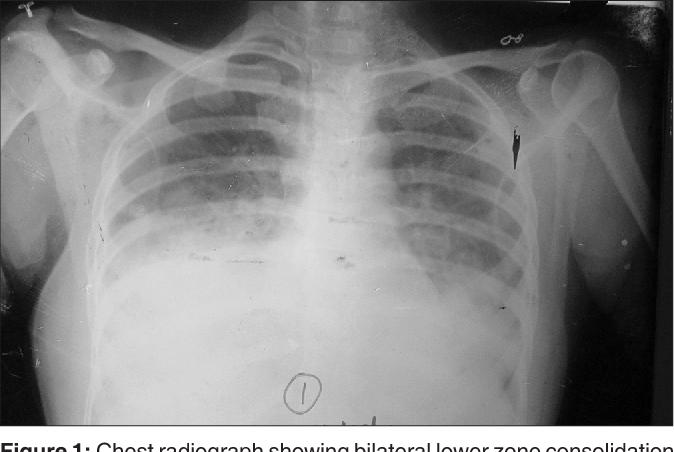

Kerosine ingestion is also known as paraffin ingestion.Thank you for reading this post, don't forget to subscribe! Kerosine is an oily petroleum

Thank you for reading this post, don't forget to subscribe! Pneumonia refers to infection of the lung. The lung is the organ